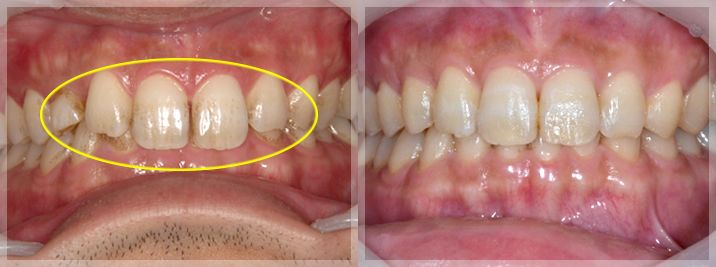

すれ違い咬合の改善

| 術前 | 術後 |